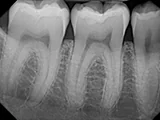

| X-Ray Example |

X-ray taken with the Pro Sensor |

Dental X-Ray Comparison

DentiMax

X-ray taken with the DentiMax sensorOpen Sensor